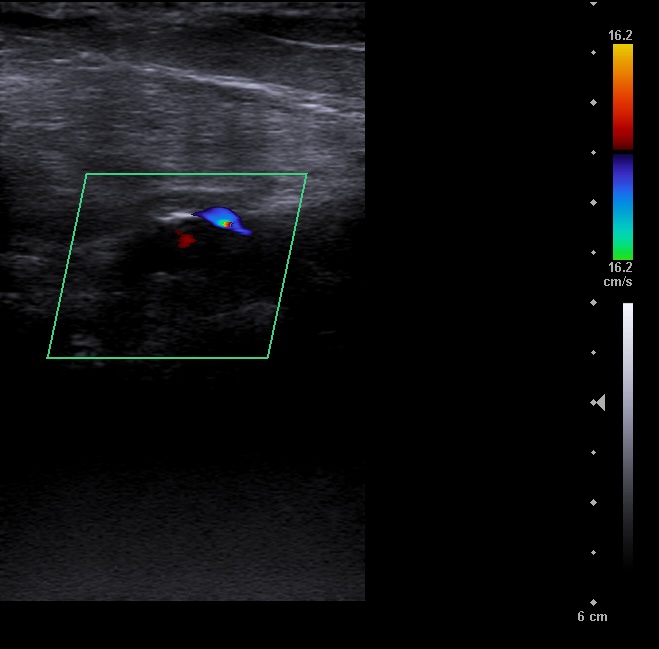

En la ecografía se aprecia vena femoral común, vena femoral superficial, vena safena mayor y vena safena menor con diámetro y flujo normal, llenado total de la luz venosa con el Doppler color y compresibilidad adecuada.

Vena poplitea no compresible, con material ecogénico en su interior y ausencia de flujo con Doppler color.